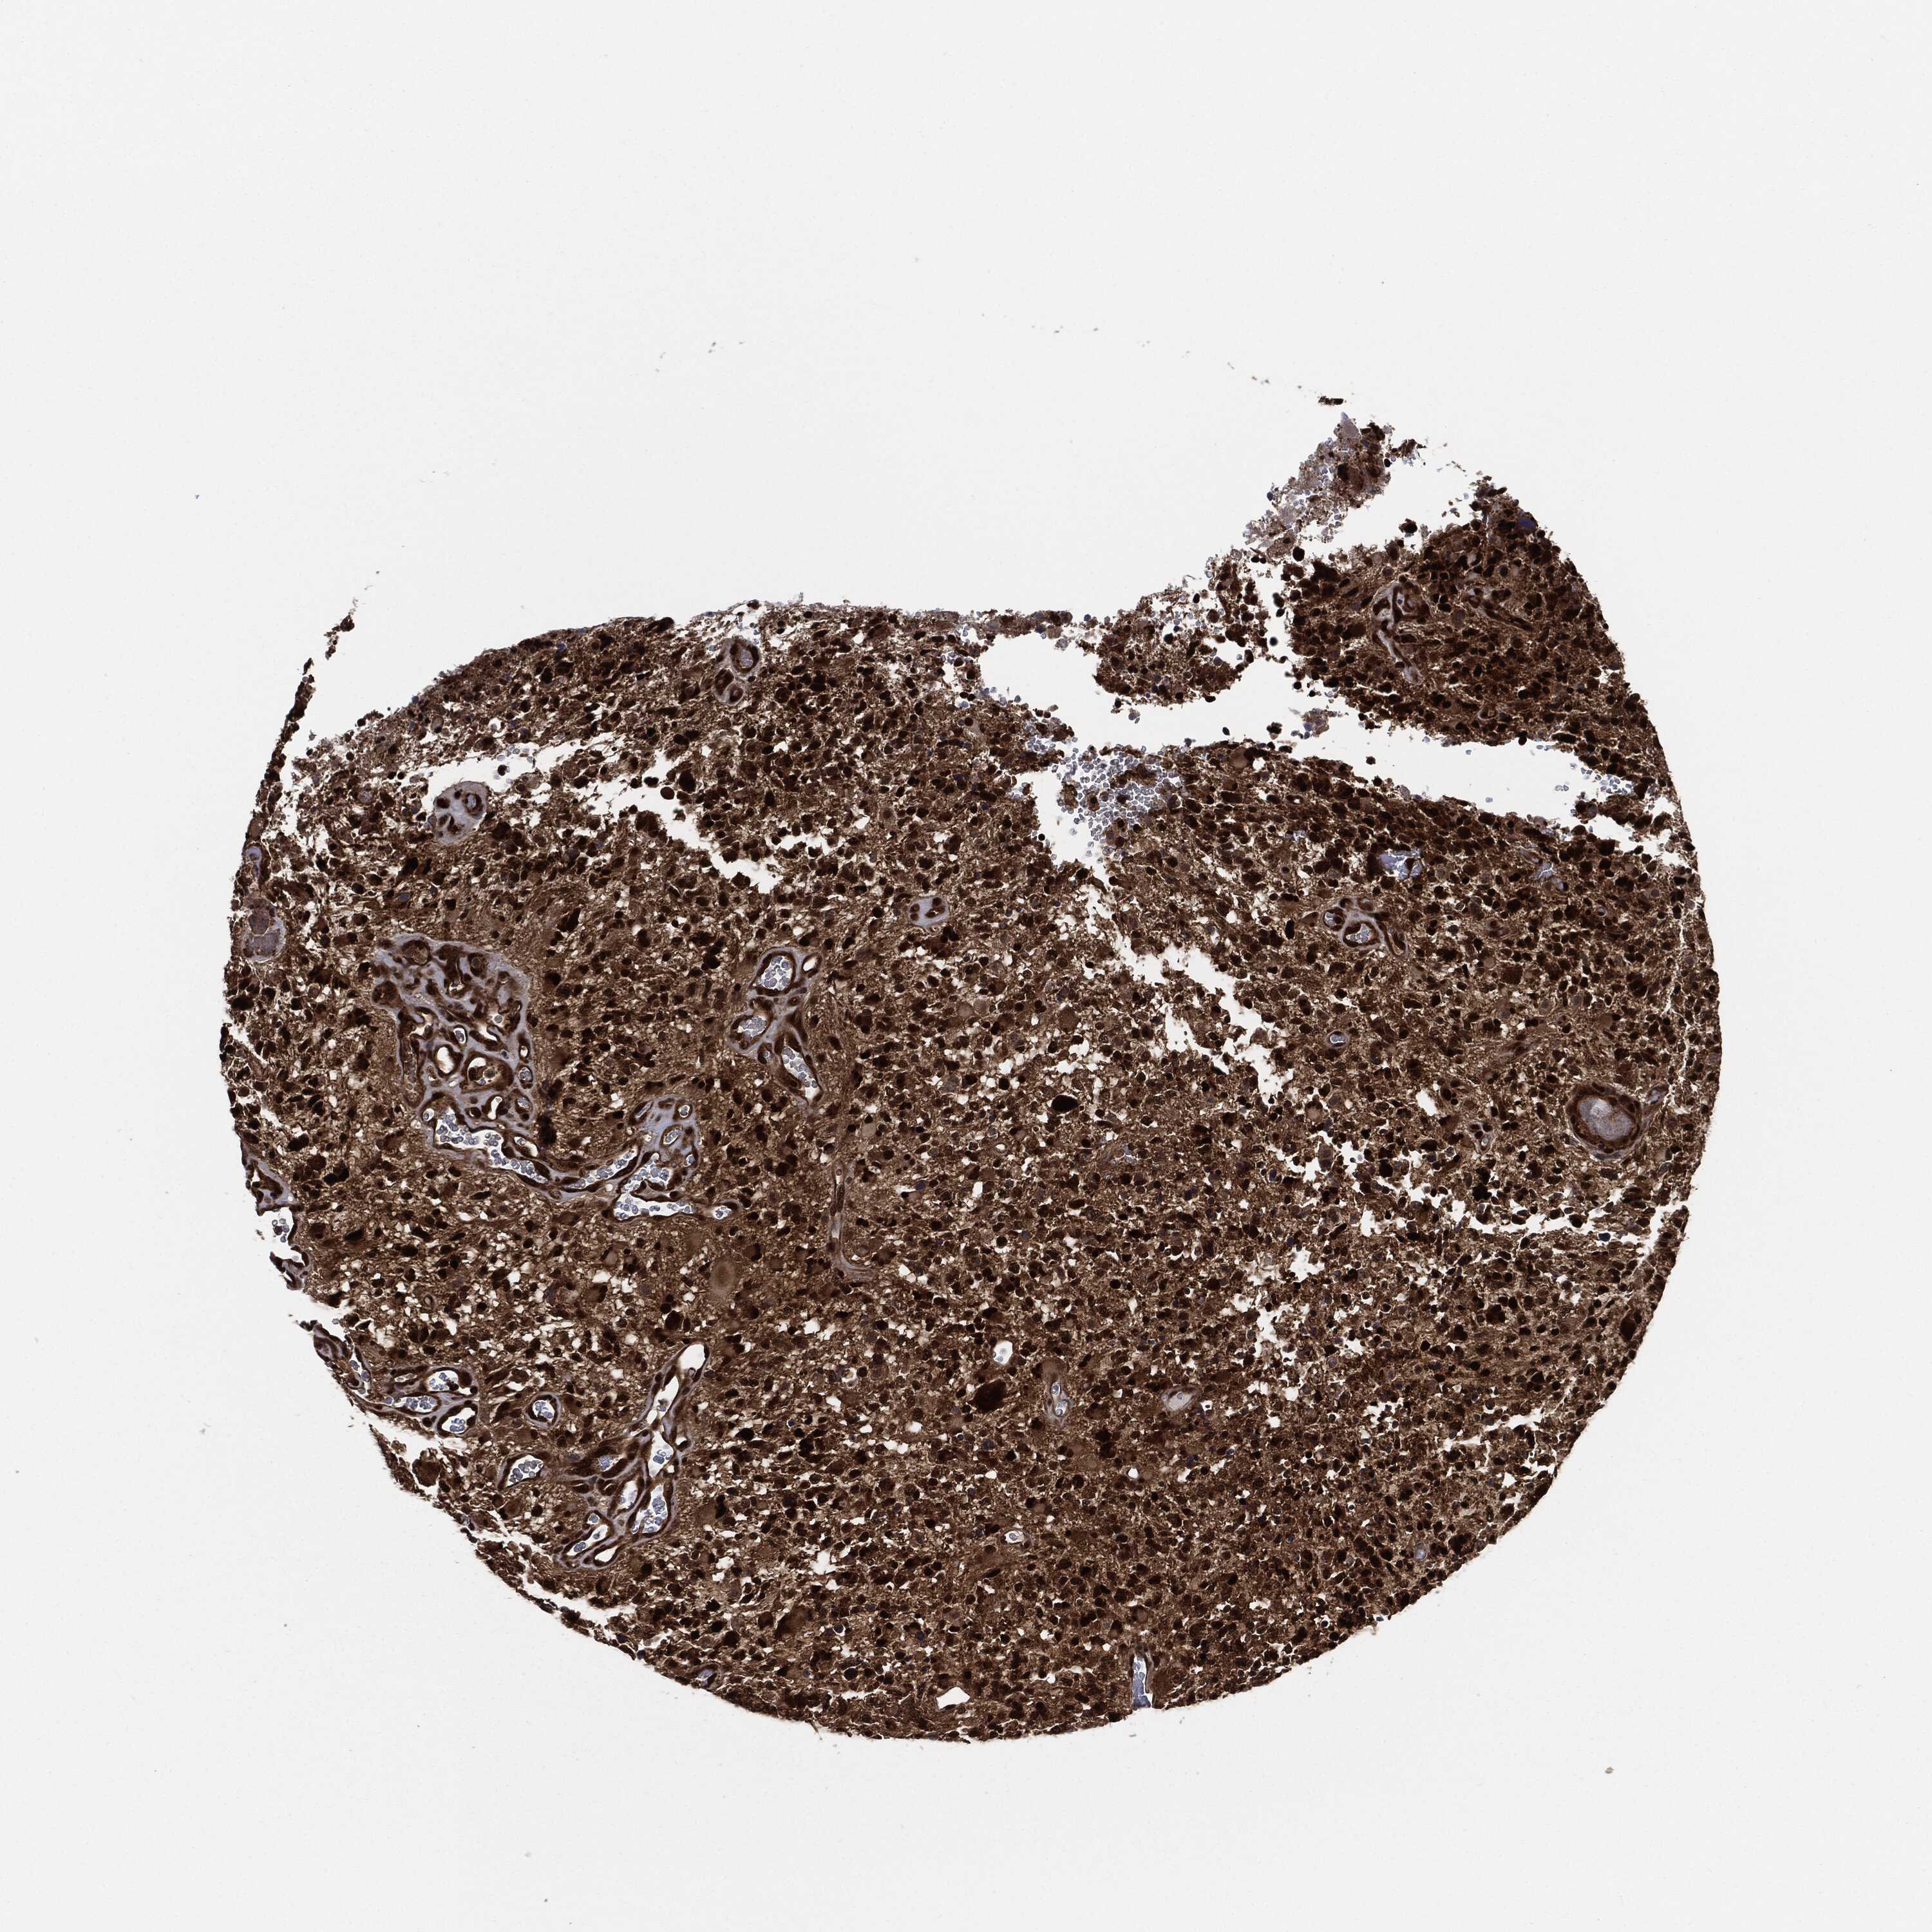

GLIOMA - Protein expressioni

A mouse-over function shows sample information and annotation data. Click on an image to view it in a full screen mode. Samples can be filtered based on level of antibody staining by selecting one or several of the following categories: high, medium, low and not detected. The assay and annotation is described here.

Note that samples used for immunohistochemistry by the Human Protein Atlas do not correspond to samples in the TCGA dataset.

Antibody stainingi

Antibody staining in the annotated cell types in the current human tissue is reported as not detected, low, medium, or high, based on conventional immunohistochemistry profiling in selected tissues. This score is based on the combination of the staining intensity and fraction of stained cells.

Each image is clickable and will lead to virtual microscopy that enables deeper exploration of all samples and also displays staining intensity scores, fraction scores and subcellular localization as well as patient and tissue information for each sample.

Antibody HPA034635

Antibody HPA069977

Antibody HPA071875

Antibody CAB009108

Staining

High

Medium

Low

Not detected

Intensity

Strong

Moderate

Weak

Negative

Quantity

>75%

75%-25%

<25%

None

Location

Nuclear

Cytoplasmic/membranous

Cytoplasmic/membranous,nuclear

Glioma, malignant, Low grade

Glioma, malignant, High grade